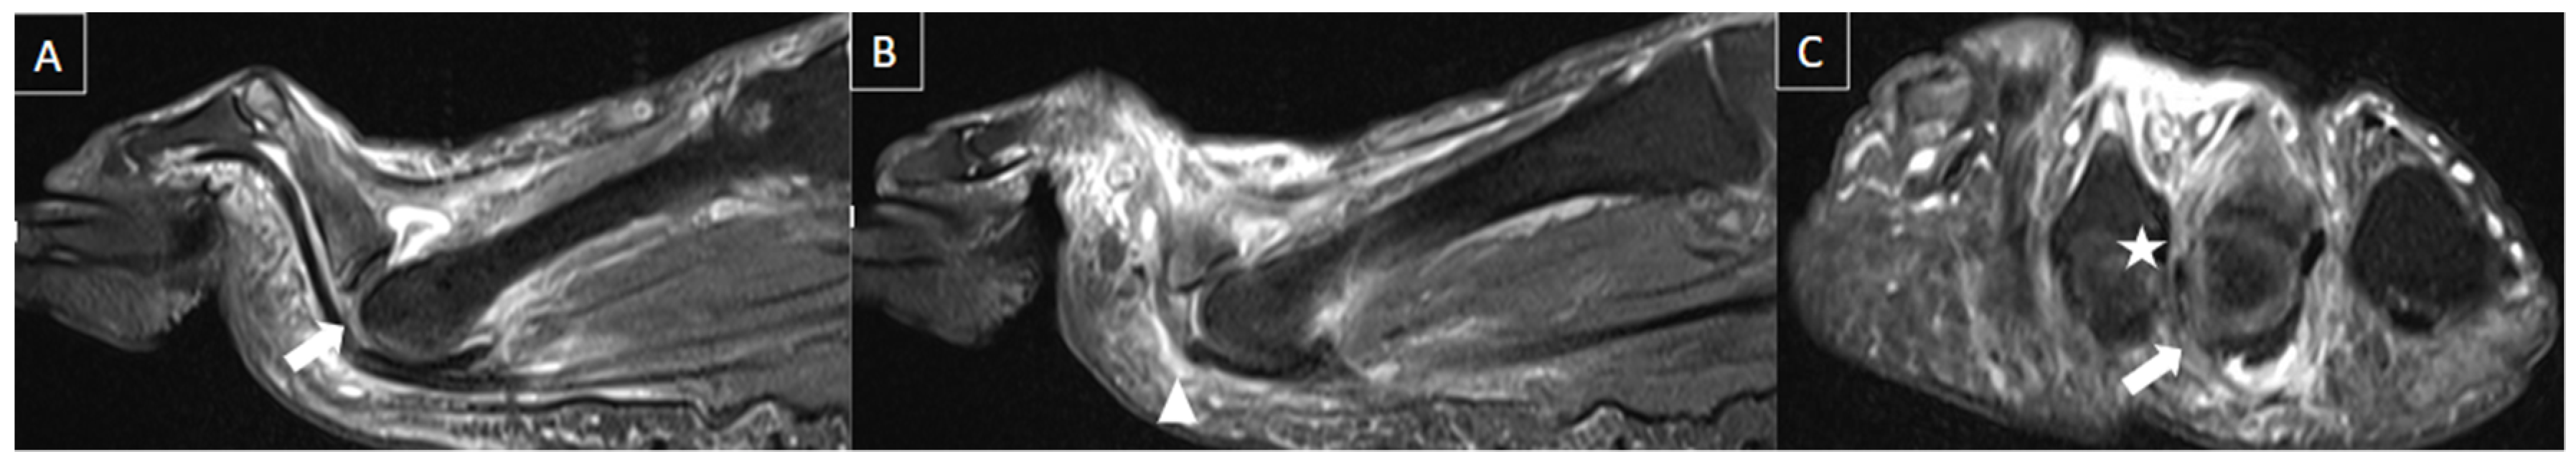

6.4. Plantar Fasciitis